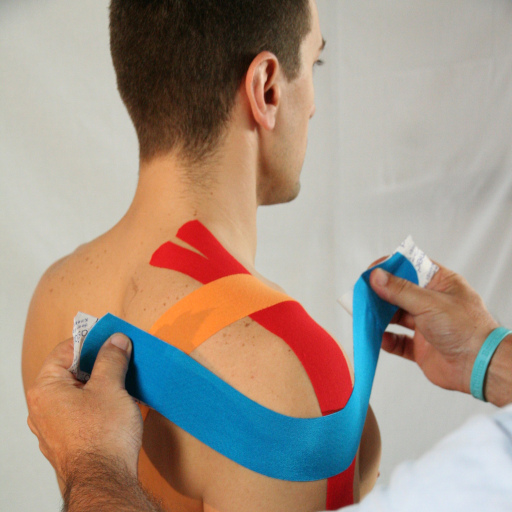

- Taping kinesiologico drenante della coscia sinistra